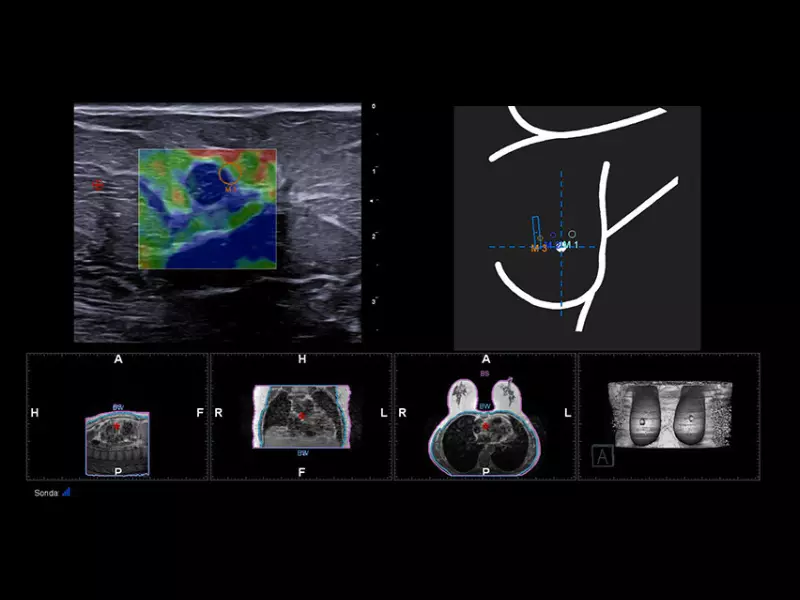

MyLab™9 Platform - MSK BodyMap and real-time XFlow on X-Ray extremities

MyLab™9 Platform - MSK BodyMap and real-time XFlow on X-Ray extremities